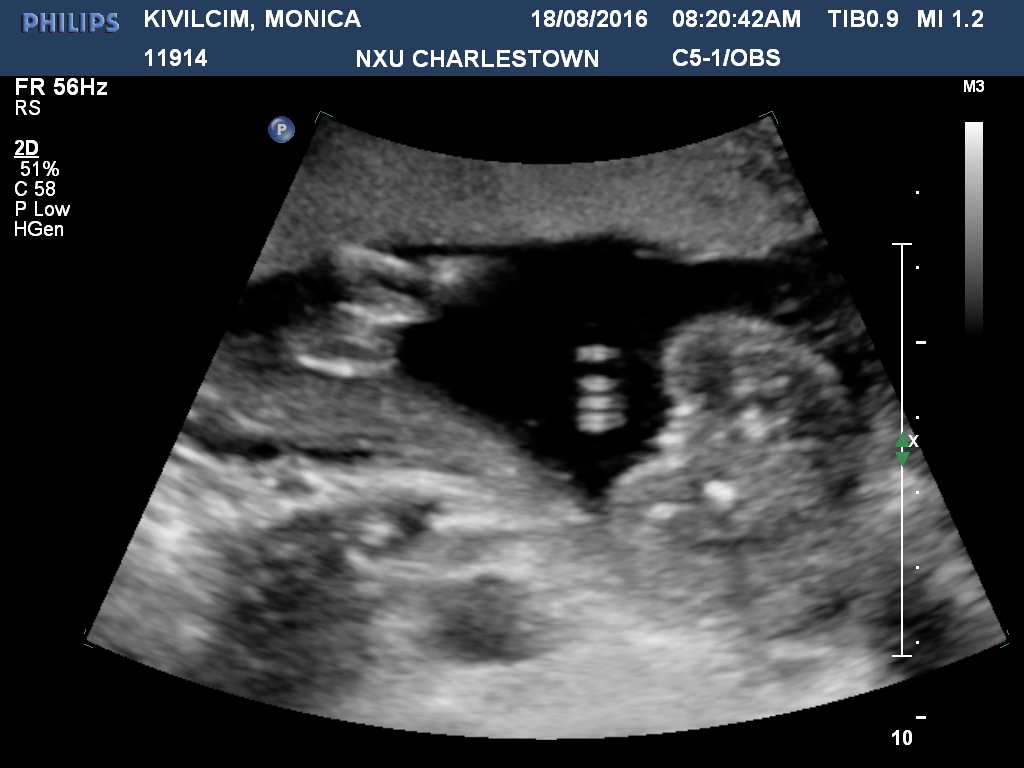

Looks all girl! Congratulations, go pink mad! :)